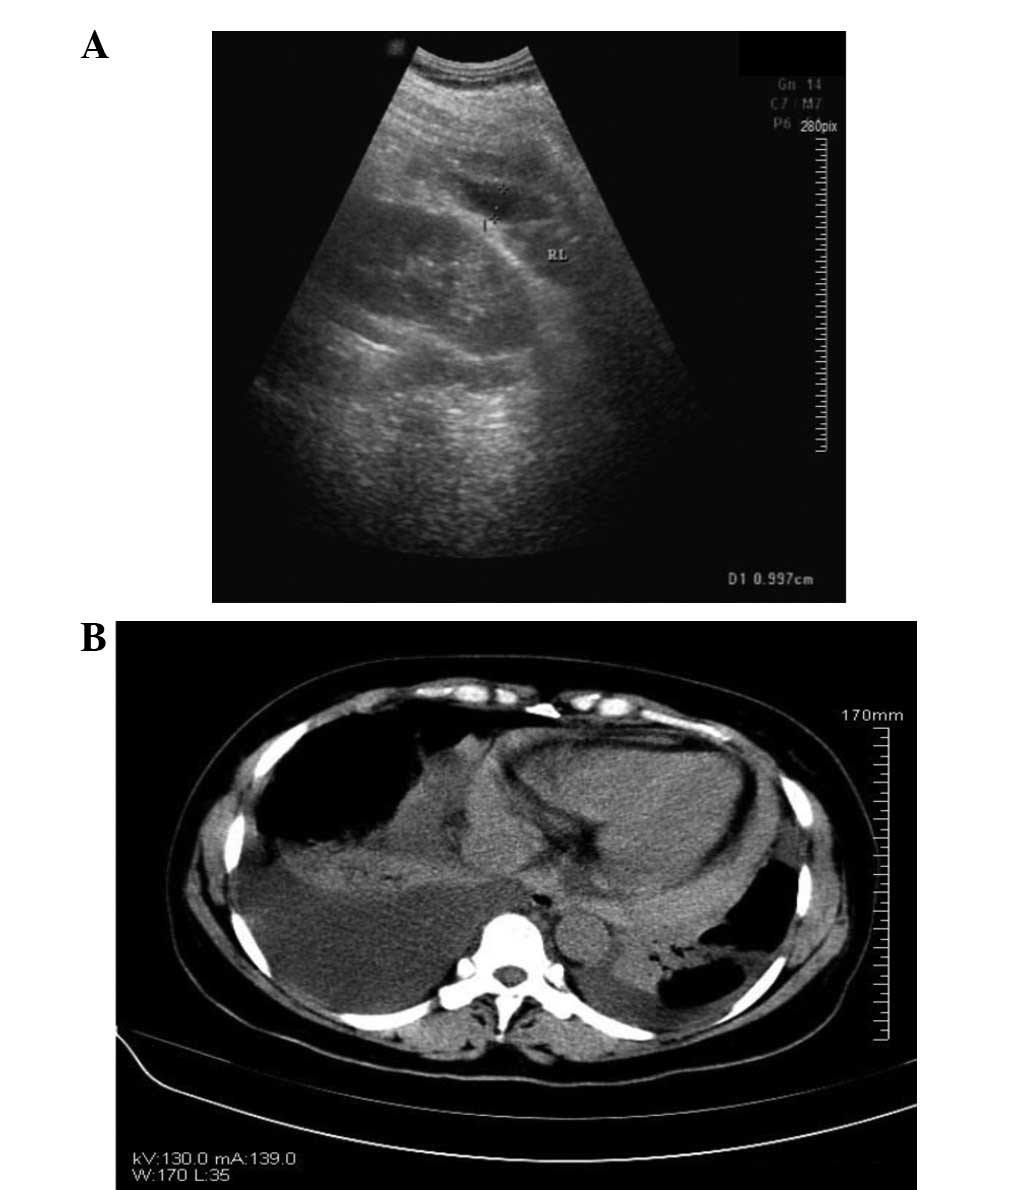

Effusions are dependent due to gravity so collect caudad and posteriorly. In the presence of several voiced cavities, several drainage tubes are used. Ultrasound signs of pleural effusions. Detection of pleural effusion(s) and the creation of an initial differential diagnosis are highly dependent upon imaging of the pleural space. A pleural effusion should have a meniscus. Pleural effusions are generally classified as transudates or exudates, based on the mechanism of fluid formation and pleural fluid chemistry. I also thought that chf was bilateral pleural effusion but i guess you can have unilateral too. Before pleural ultrasound, a respiratory expert (gh) reviewed each patient's most recent chest radiographs to determine which side of the thorax to assess via ultrasound. The drainage tube, as a rule, is installed under the control of fluoroscopic examination, ultrasound or ct. Potential mechanisms of fluid increased interstitial fluid in the posteroanterior and lateral chest radiographs usually confirm the presence of a pleural effusion, but if doubt exists, ultrasound or computed. If it is completely flat this may suggest a concurrent pneumothorax. If you have a patient with a suspected pleural edema and/or bilateral effusions with increasing severity. Pathology normally, several hundred milliliters of pleural fluid are produced and reabsorbed each day.

If a unilateral pleural effusion is thought to be exudative, british thoracic society guidelines suggest pleural fluid aspiration (diagnostic) which is usually performed under ultrasound guidance.5. Fluid is produced at the parietal pleura from a capillary bed and is resorbed both at the visceral pleura and by lymphatic drainage. If you have a patient with a suspected pleural edema and/or bilateral effusions with increasing severity. Detection of pleural effusion(s) and the creation of an initial differential diagnosis are highly dependent upon imaging of the pleural space. Before pleural ultrasound, a respiratory expert (gh) reviewed each patient's most recent chest radiographs to determine which side of the thorax to assess via ultrasound. In patients with bilateral pleural effusion. In the presence of several voiced cavities, several drainage tubes are used. Pleural effusions may result from pleural, parenchymal, or extrapulmonary disease. A narrative review from diagnosis to treatment. Chest ultrasound to evaluate pleural effusion. Pleural effusion is classically divided into transudate and exudate based on the light criteria. Ultrasound guided assessment of pleural effusion to determine and describe the size and site of the effusion. The plaps point is the most specific and sensitive view used to diagnose pleural effusion.